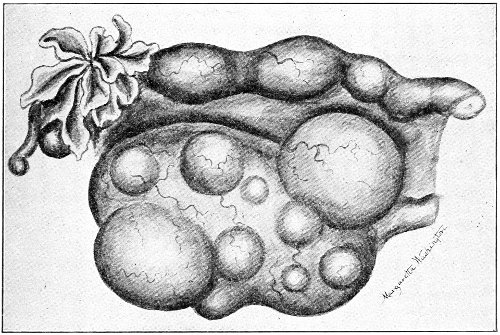

Gynecology is the study of diseases peculiar to women. As woman possesses organs which man has not, and as the parts—physiological and social—that she plays in life differ from those played by man, we should expect to find her afflicted with a certain number of diseases, peculiar to her, which are dependent upon her anatomy, physiology, and mode of life. Such diseases occur in barbarous as well as in civilized women; and similar diseases, peculiar to the female, occur in the lower animals. Thus, in the cow and the mare we find tumors of the vagina, prolapse of the vagina and uterus, fibroid tumors, sarcoma and cancer of the uterus, and some forms of ovarian cysts. Cysts of the tubes and the ovaries are exceedingly common in old mares; cats and goats are similarly affected.

Fibroid tumors of the uterus, which are so common among the colored women of this country, are said by Tait to be unknown among their African cousins, who are removed by but a few generations.

Celibacy is an unnatural state and a common cause of disease. Certain forms of fibroid tumors of the uterus are more common in single than in married women, and more common in sterile than in childbearing women. And the painful cirrhotic ovaries of the old maid are the result of the unceasing menstrual congestions never relieved by pregnancy and lactation. 19